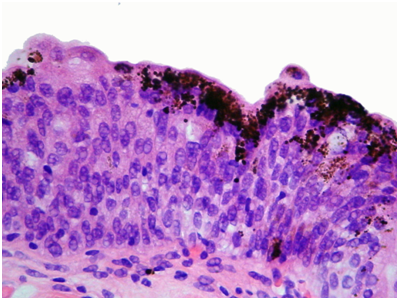

Clinical examination and radiological investigations including and ultrasound scan and a computerised axial tomogram scan (with intravenous contrast) of his urinary system were unremarkable. Routine blood tests including full blood count, urea, electrolytes and prostate specific antigen were normal. Urinalysis had revealed microscopic haematuria. There was no evidence of infection on urinalysis, mid-stream urine microscopy and culture. Urine cytology x 3 were normal. Flexible cystoscopy revealed several small, evenly pigmented, flat, brown/black lesions, measuring between 3 and 5mm in diameter, scattered throughout the bladder mucosa, with the greatest density and size of the lesions at the bladder base (Figure 1). Cold cup and subsequent resection biopsies were undertaken. There was no suggestion that the prostate could have been the source of his haematuria. Histopathology of both specimens showed many granules of golden brown pigment of varying size in the urothelial cells and within histiocytes in the underlying lamina propria (Figures 2&3).

No melanocytes were visible on routine staining with haematoxylin and eosin or with the immunoperoxidase stain S100 or with electron microscopy. The urothelium was not dysplastic. Some areas had metaplastic changes of cystitis cystica. The pigment was negative with Perl’s and with periodic acid Schiff (PAS) stains, excluding haemosiderin and lipofuscin respectively. Masson stain was positive, and bleaching removed the pigment, together indicating that the pigment was melanin. Electron microscopy showed that the pigment was bound in lysosomes and that there were no melanosomes (Figure 4). The final histopathological diagnosis was melanosis of the urinary bladder.